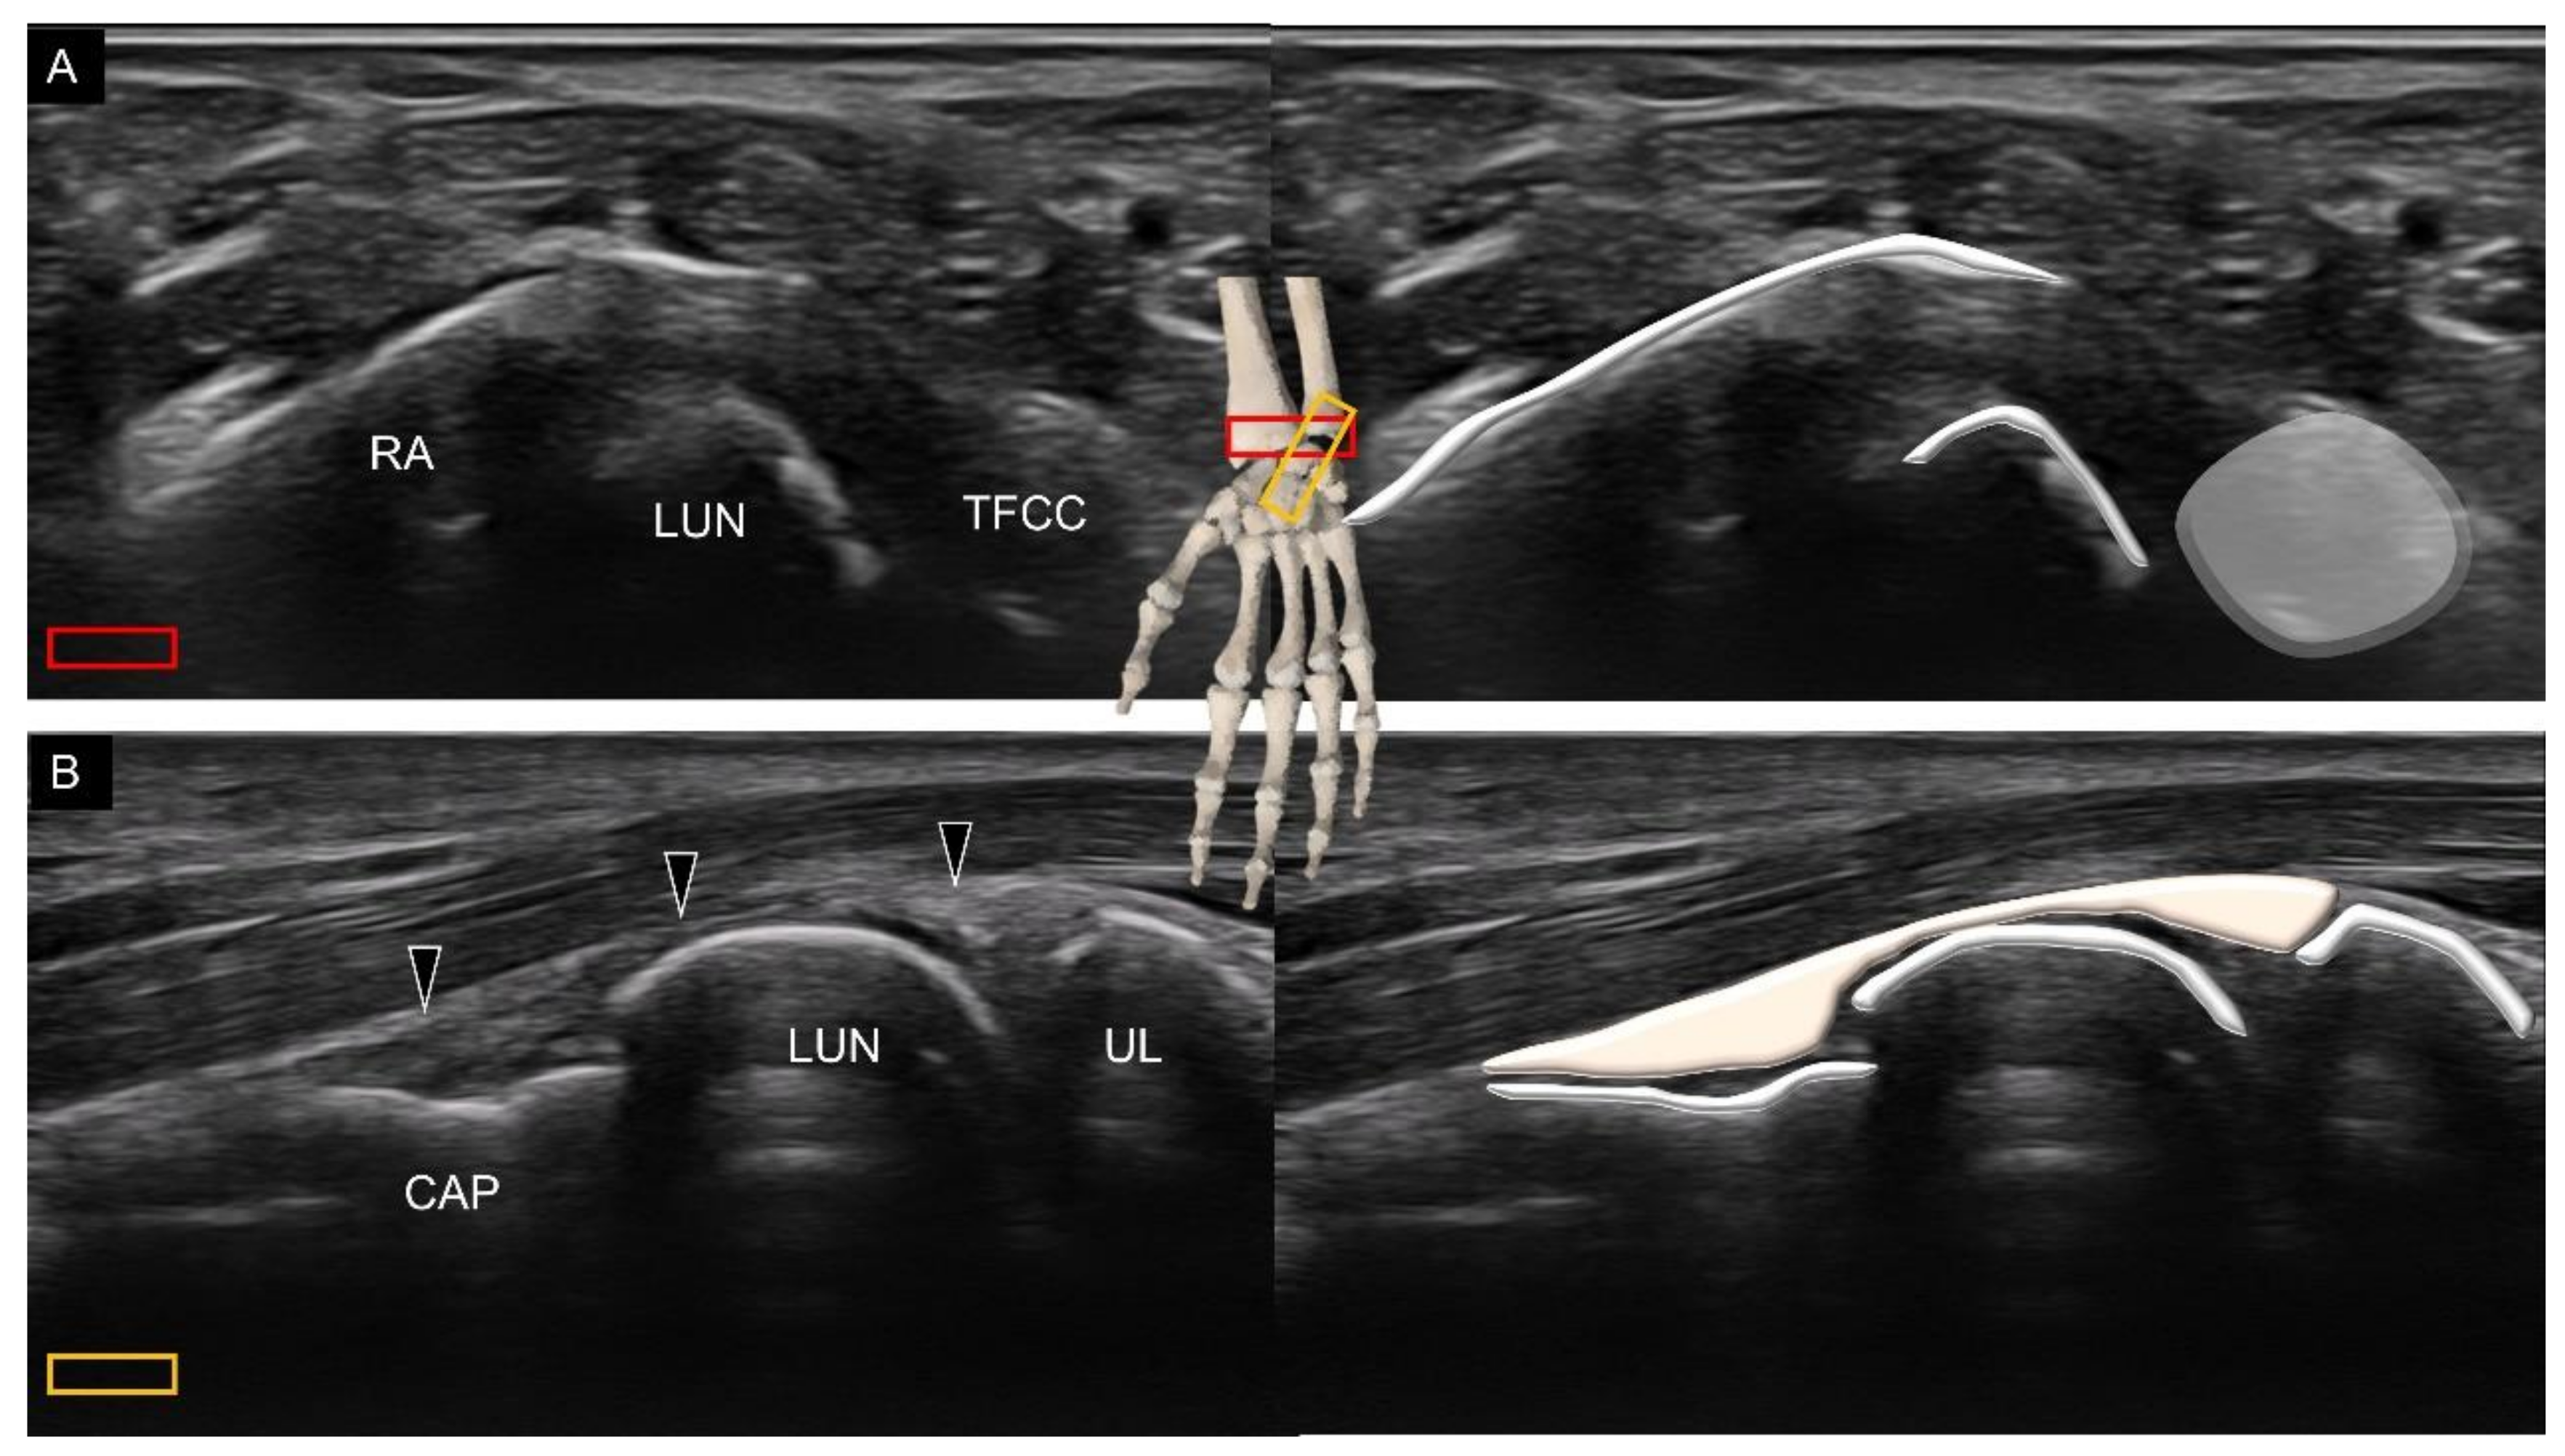

3. Sonoanatomy of Volar Extrinsic Carpal Ligaments

3.2. Attachment to the Lunate

3.3. Attachment to the Triquetrum